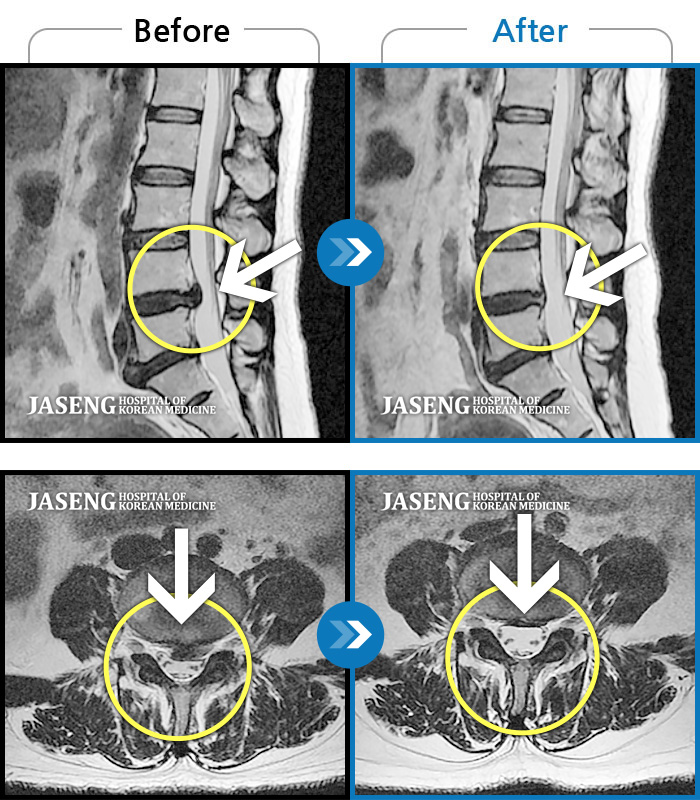

허리디스크

대전 · 김창연 원장

허리랑 좌측 엉덩이가 뻐근하게 많이 아프고, 허벅지와 종아리가 저림이 심해요. 걷기가 힘들어요.

촬영시기

2023.10.30 ~ 2024.07.19

2024.08.09